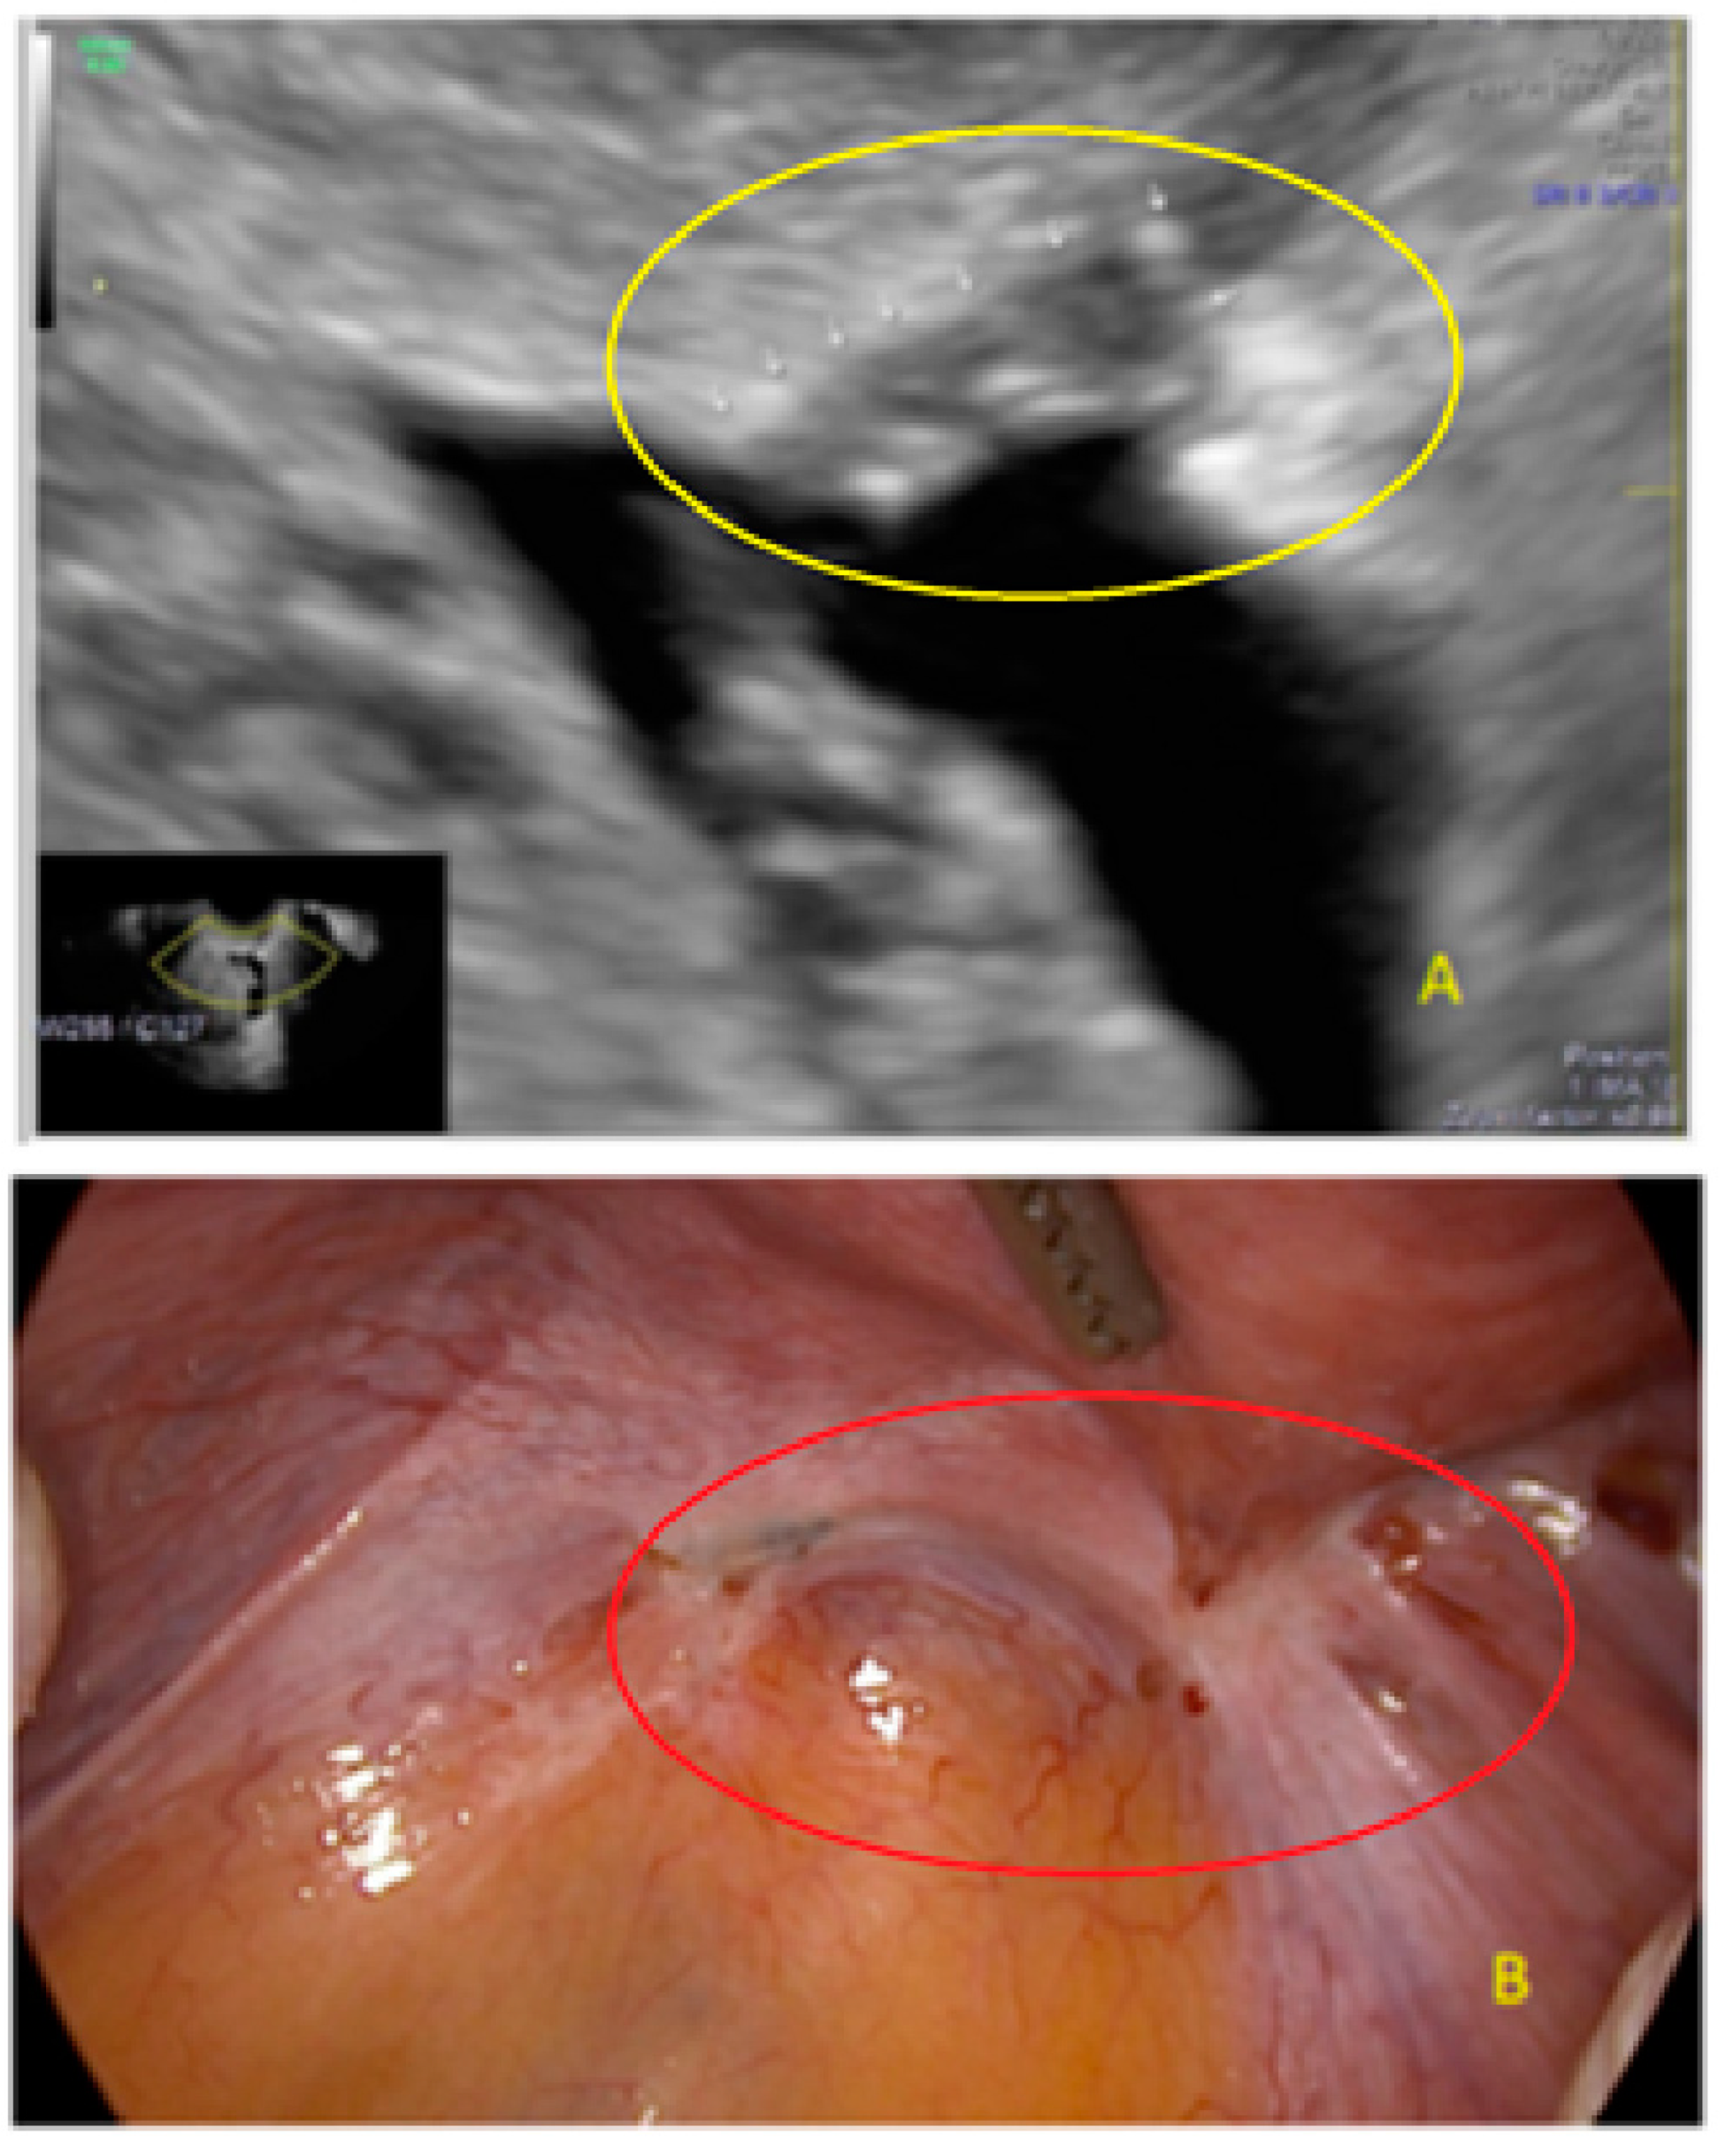

- The lesion may be convex, protruding from the peritoneal surface into the peritoneal cavity (we called this “bulging”), or it may appear as a concave defect in the peritoneum (we called this a “pocket”).

- The presence of hyperechoic foci (we called this a “pearl”).

- The presence of velamentous (filmy) adhesions associated to the lesion (we called this a “veil”).